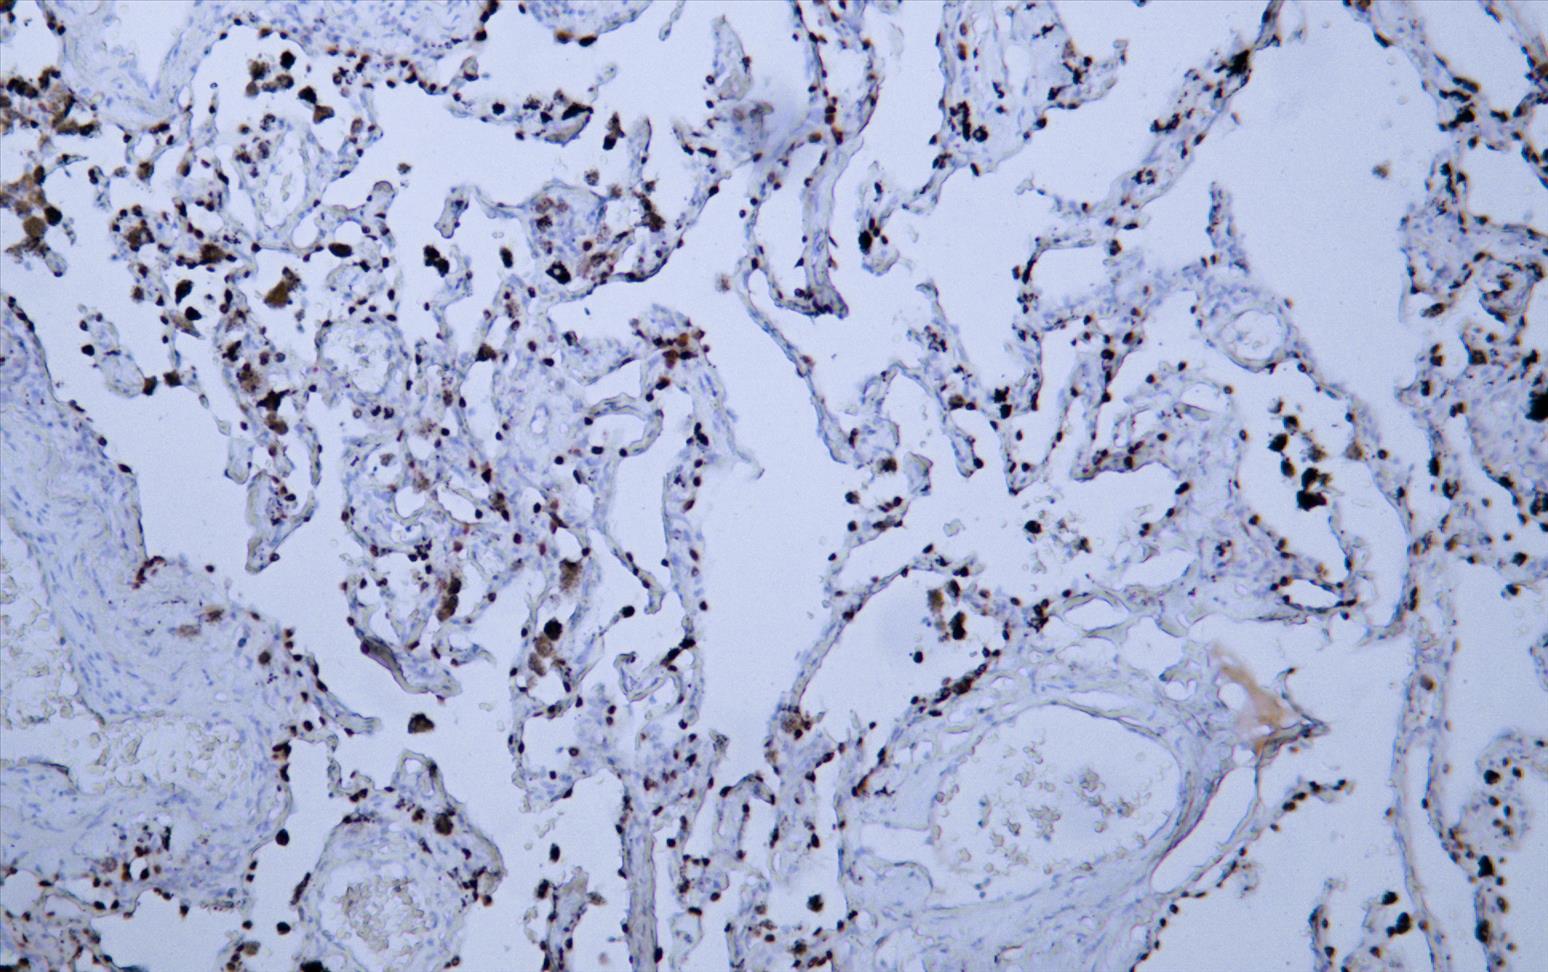

TTF1 (AB1381) mouse mAb

Application:IHC; WB; IF; ELISA

Thyroid transcription factor 1 (TTF-1) is a nuclear protein with a molecular weight of 38-40 kDa. It is the basic material for thyroid differentiation and the regulation of thyroglobulin secretion. It can promote the transport of thyroid peroxidase and iodine / sodium. TTF-1 is mainly distributed in type II alveolar epithelium, respiratory epithelium and Clara cells of thyroid and lung in adult tissues, but it is not expressed in type I alveolar epithelium. It is mainly used for the diagnosis of small cell lung cancer, the differential diagnosis of primary lung adenocarcinoma from metastatic adenocarcinoma, and the differential diagnosis of lung cancer from malignant mesothelioma and paraganglioma of pleura.

IHC; WB; IF; ELISA

IHC, 1:50-1:200 | WB, 1:500-1:2000 | IF, 1:100-1:500 | ELISA, Recommended starting concentration is 1 µg/mL. Please optimize the concentration based on your specific assay requirements.